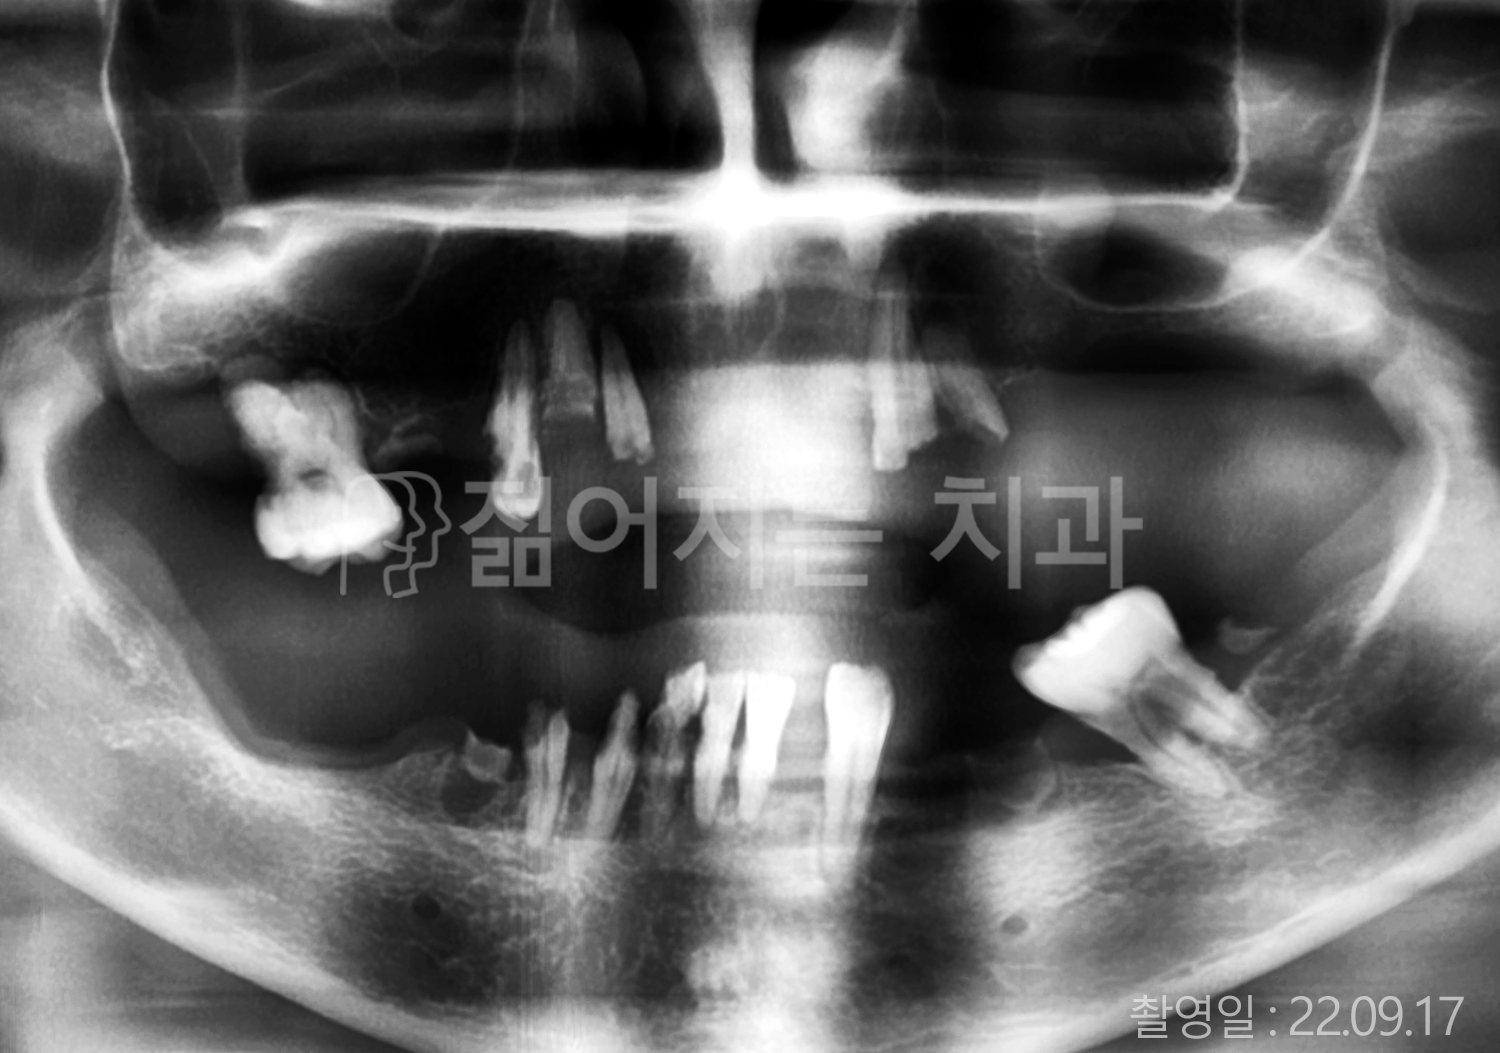

• 50대 고혈압, 당뇨, 고지혈증 전체치아 10개 이상 임플란트

• 60대 골다골증, 간경화 전체치아 10개 이상 임플란트

• 60대 고혈압, 고지혈증 전체치아 10개 이상 임플란트

• 50대 고혈압, 당뇨 전체치아 10개 이상 임플란트

• 60대 고혈압 전체치아 10개 이상 임플란트

• 60대 전체치아 10개 이상 임플란트

• 60대 고지혈증 전체치아 10개 이상 임플란트

• 40대 전체치아 10개 이상 임플란트

• 70대 전체치아 10개 이상 임플란트